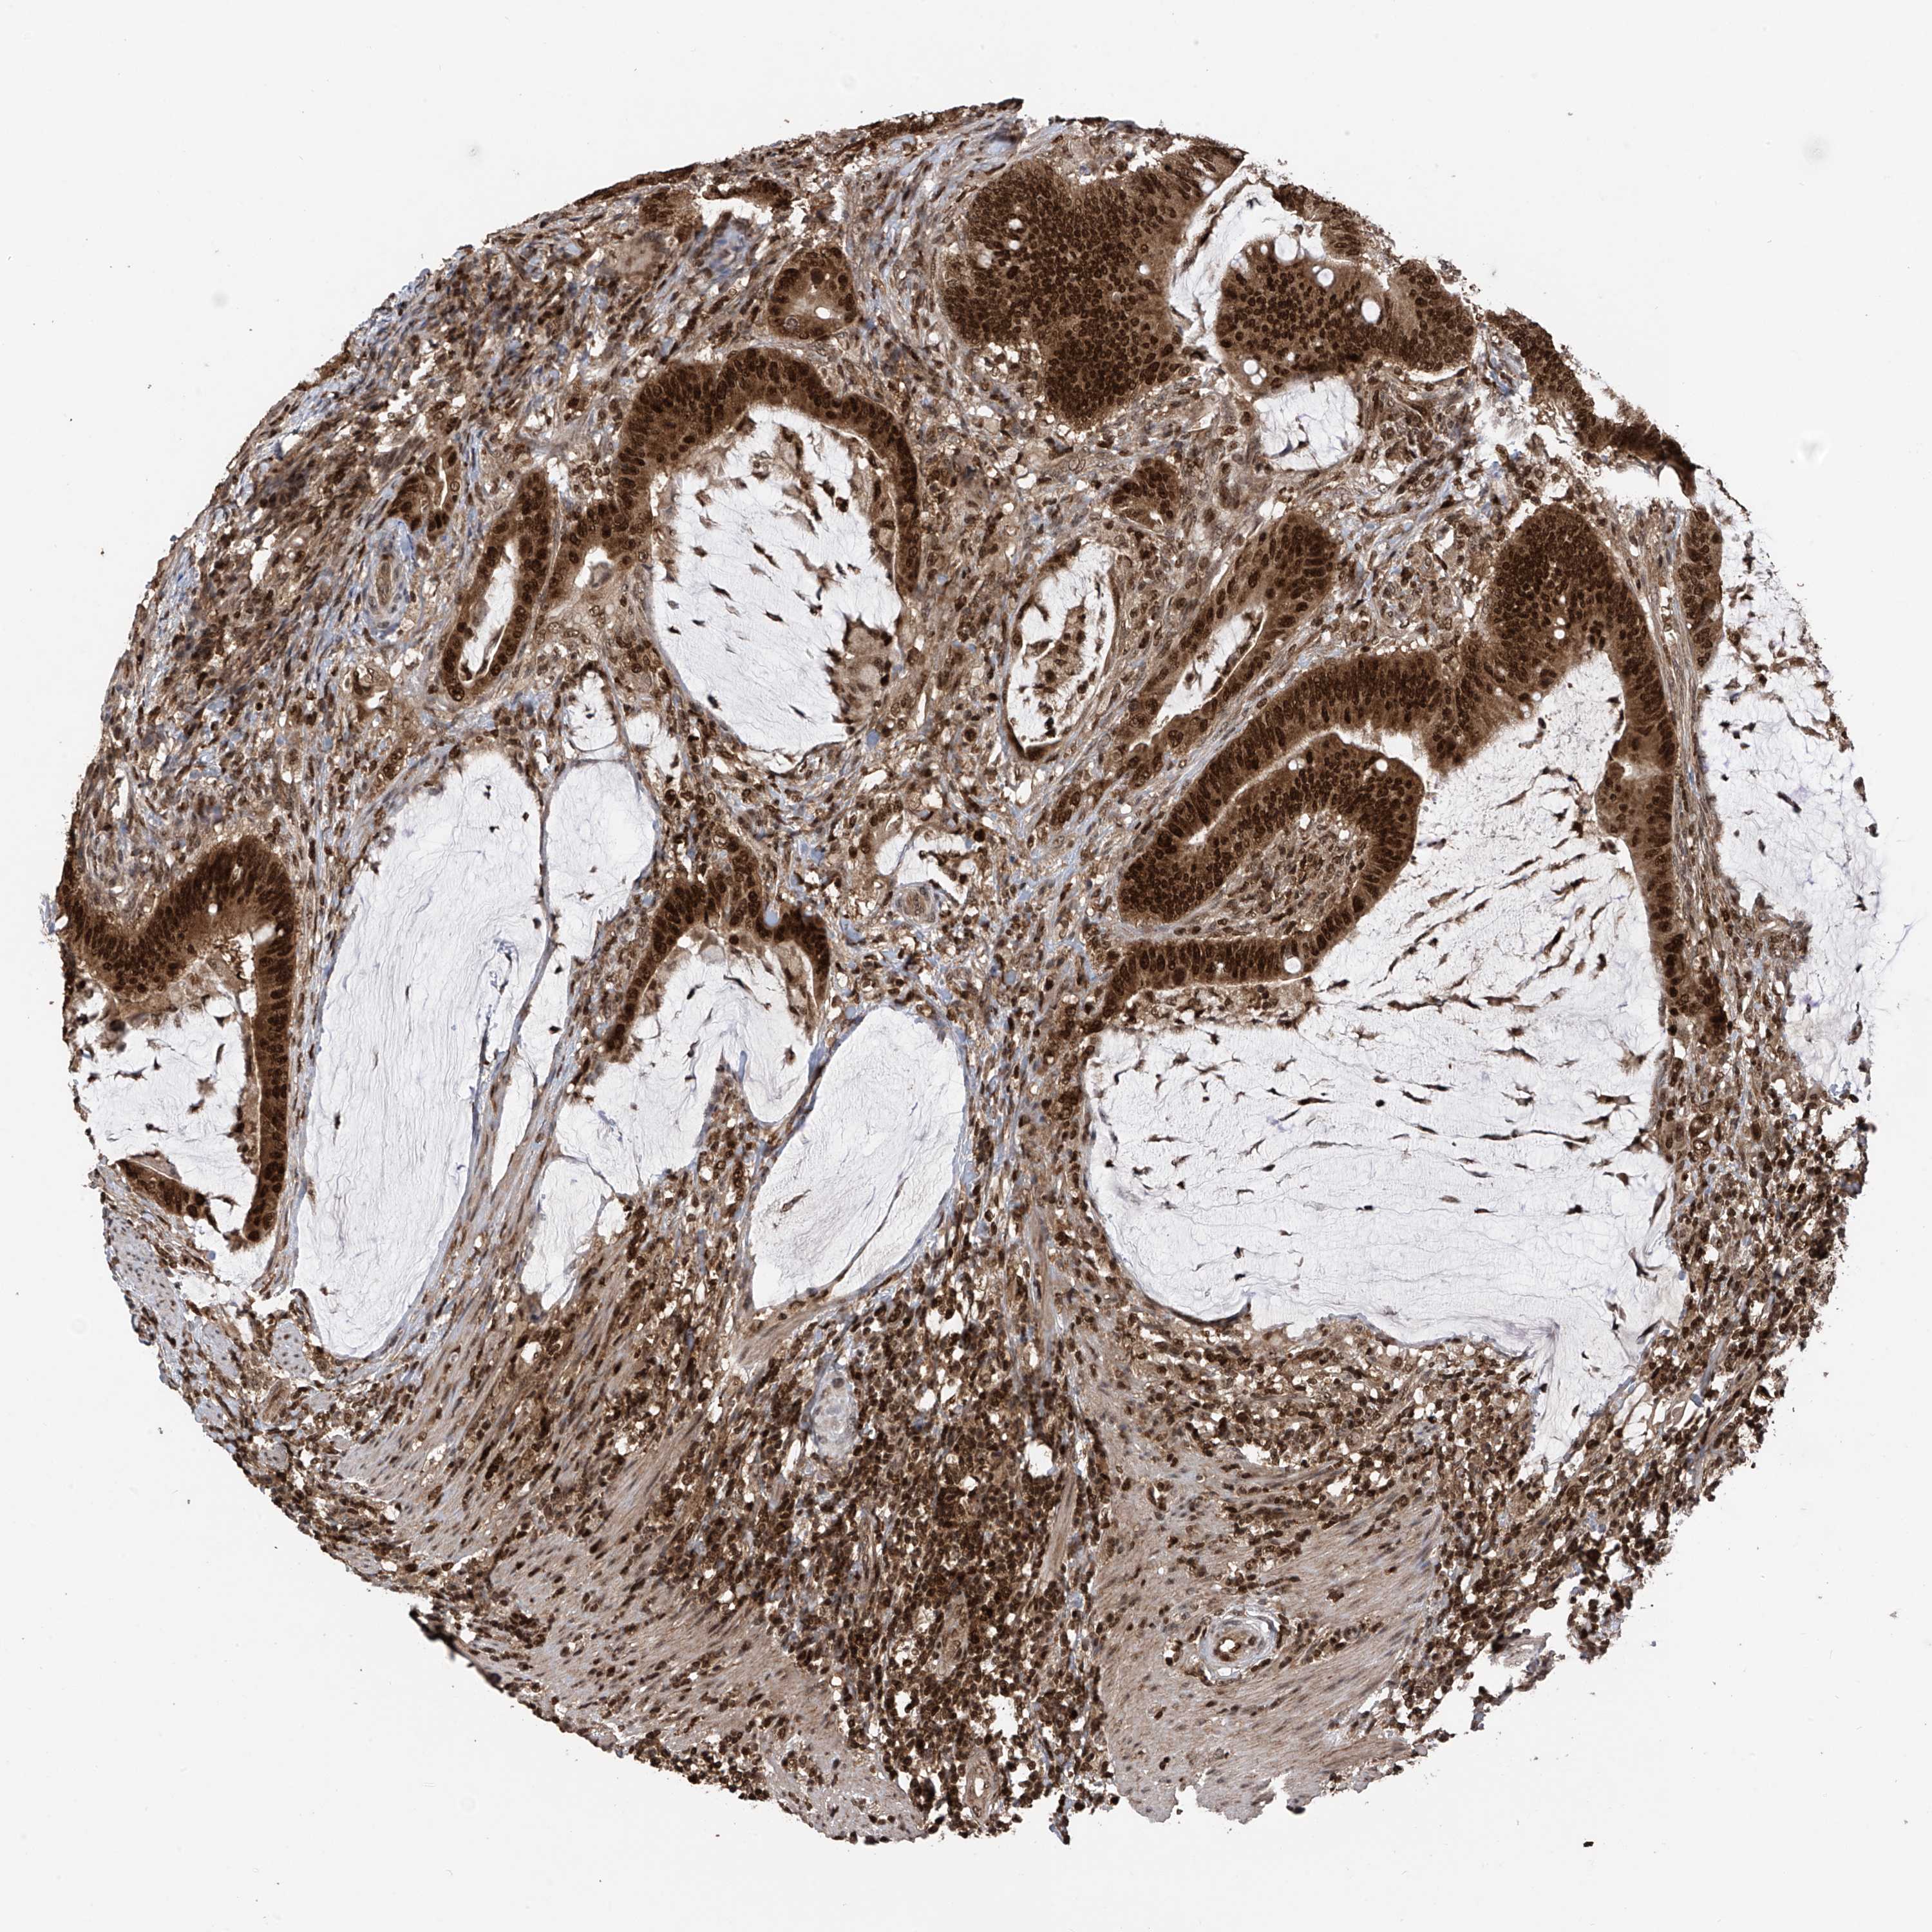

CANCER COLORECTAL CANCER Show tissue menu

Colorectal cancer

Rectum adenocarcinoma